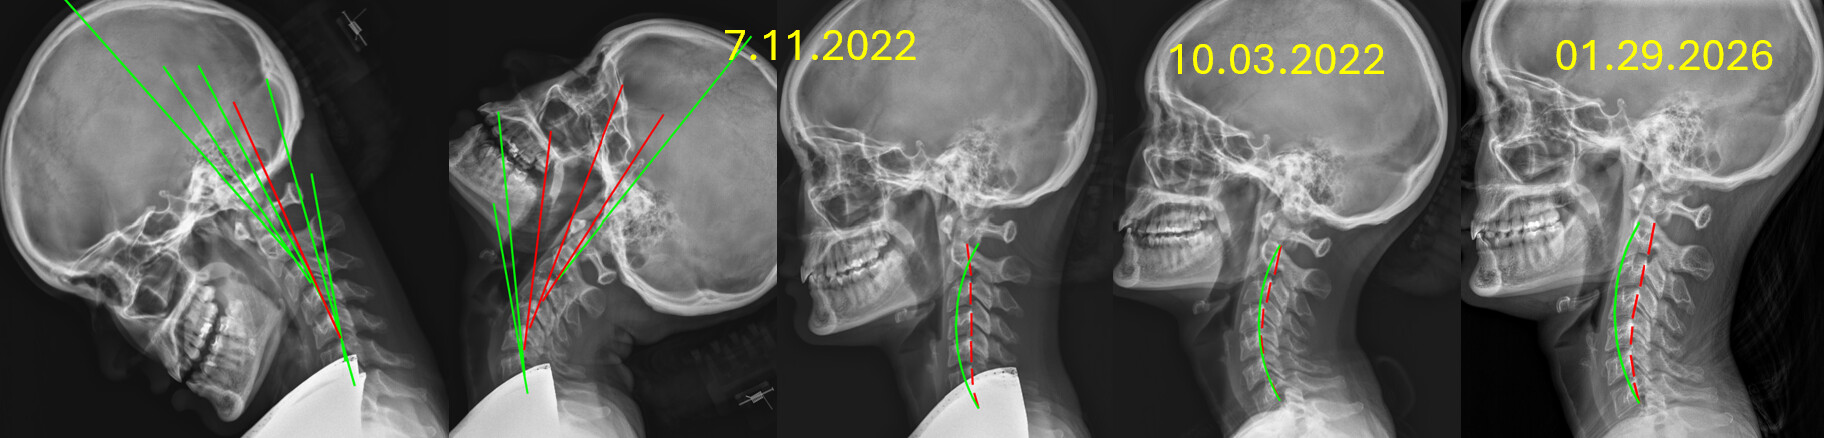

13 Month Follow Up

13 Month follow up images in our office.